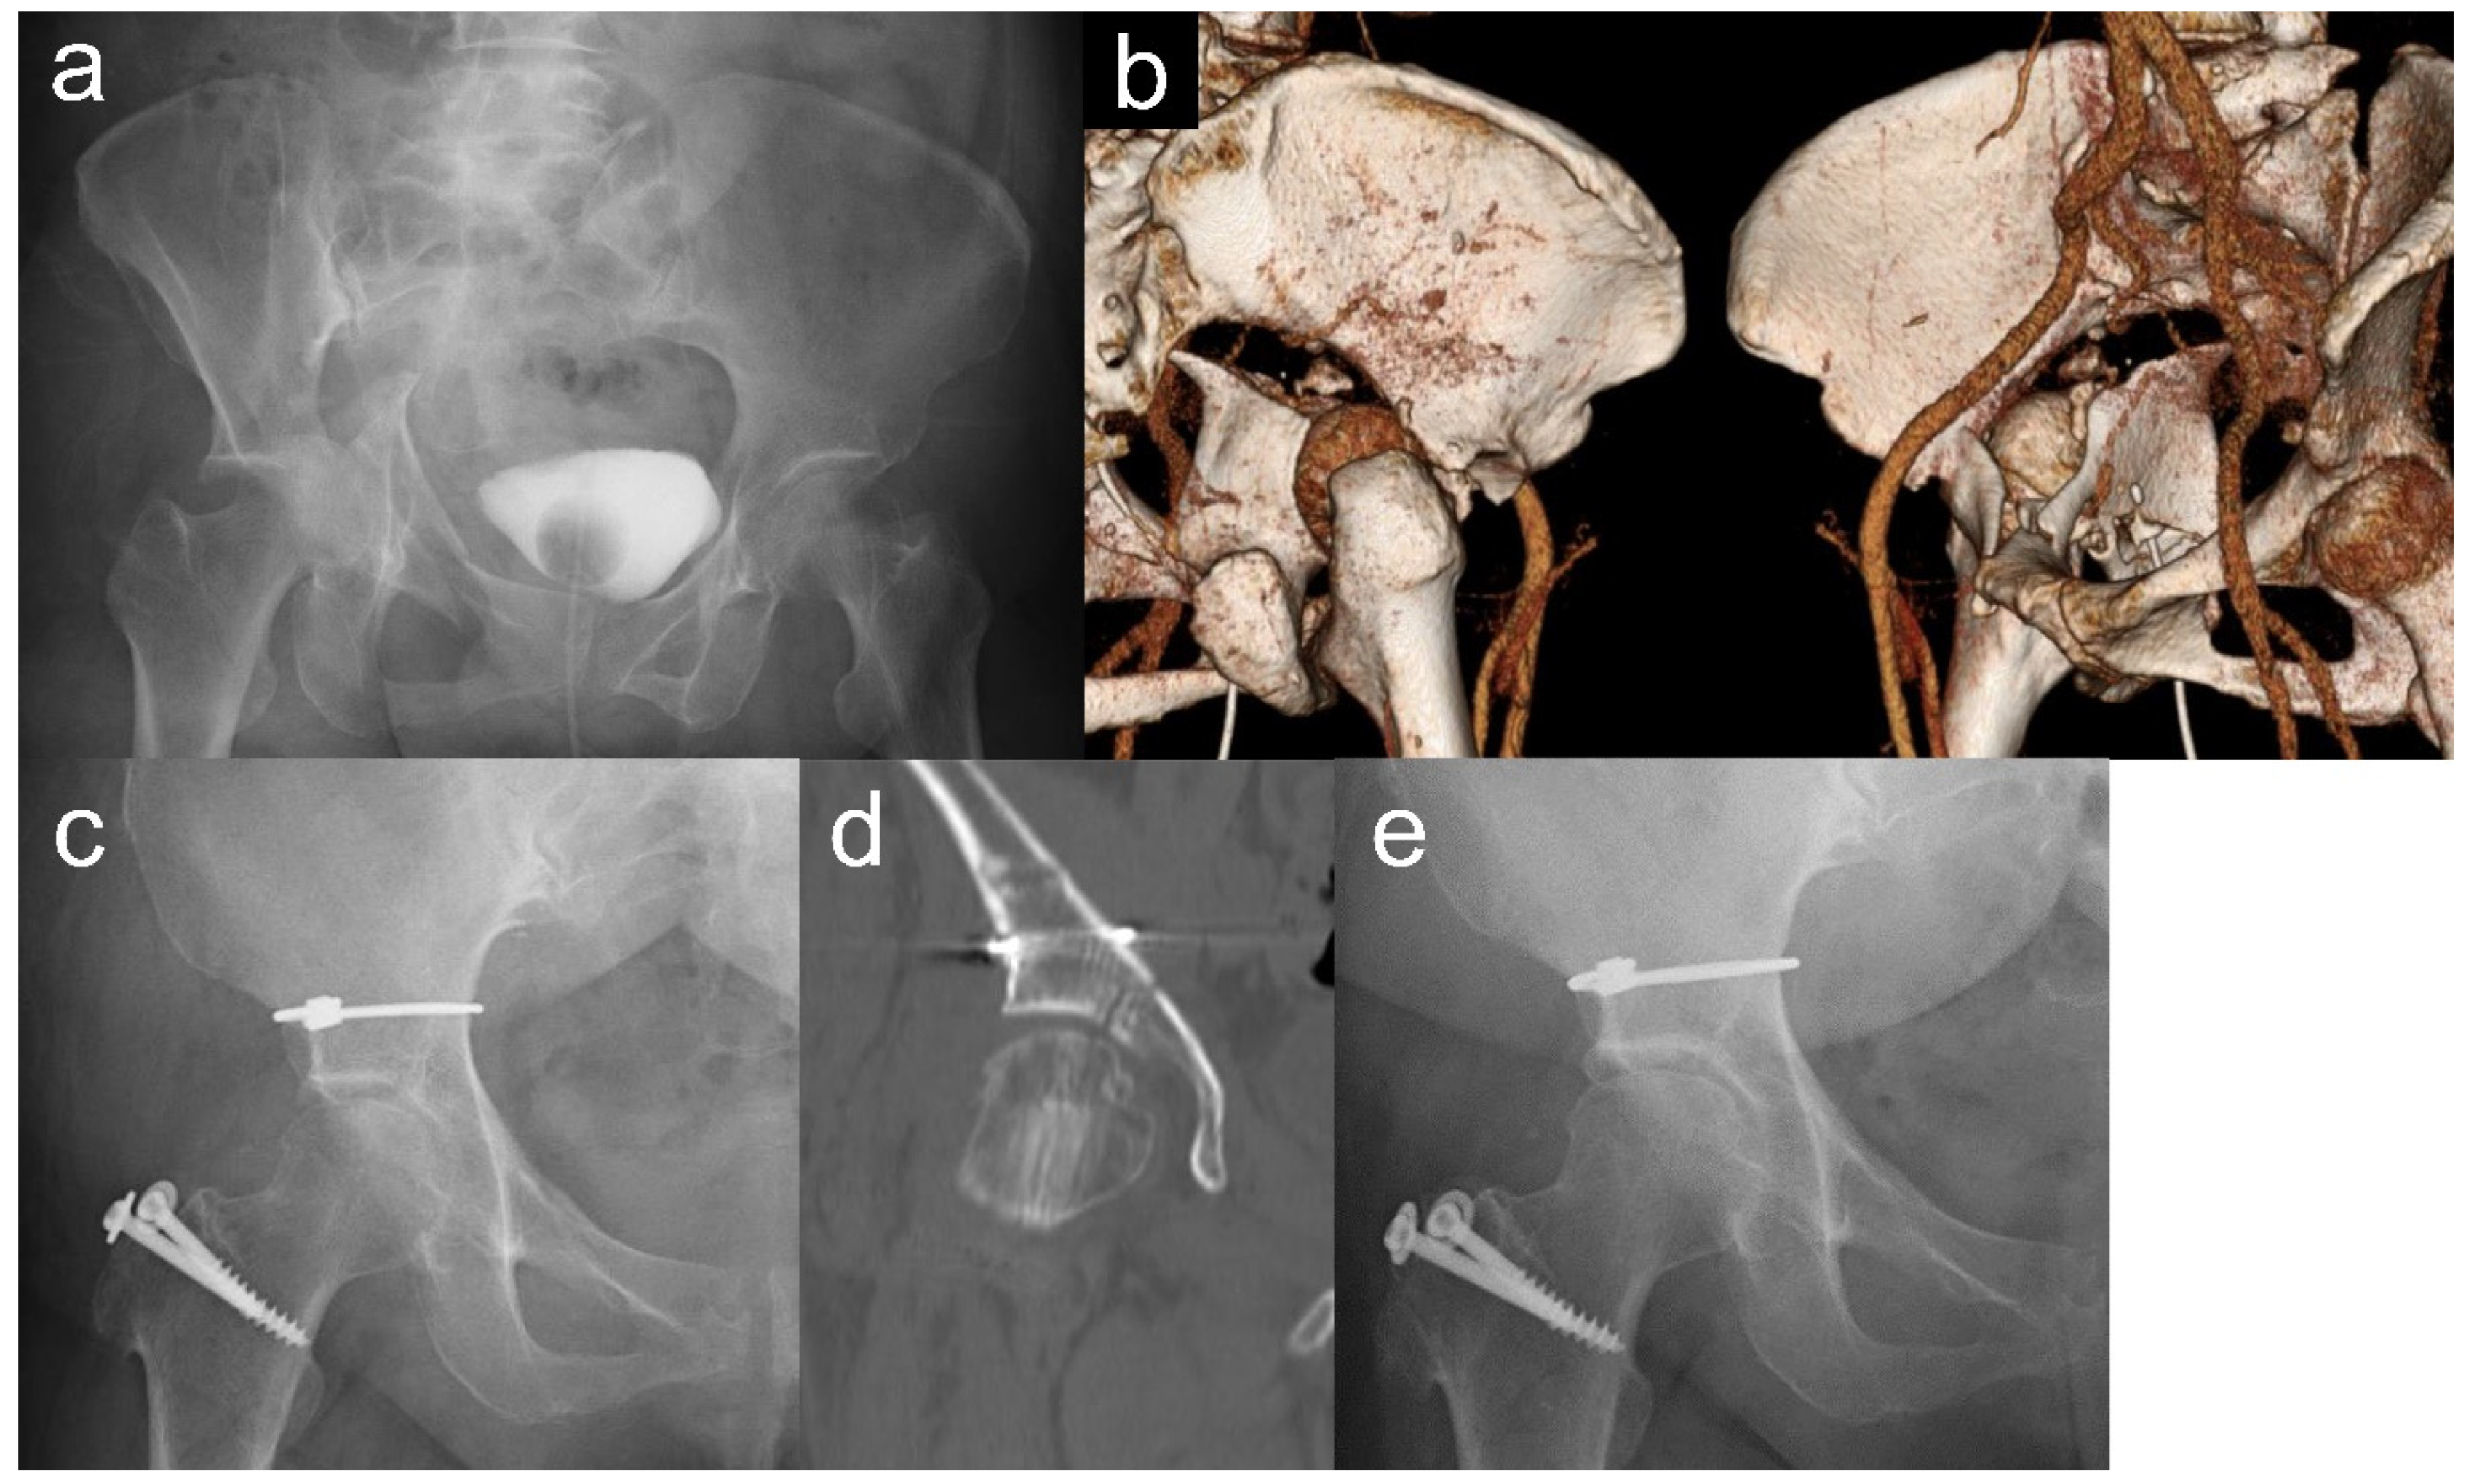

| 1 | 38 | M | 18.1 | Snowboard | 9 | 11 | BC + PW | − | 209 | 309 | Anatomical | Tönnis II | 93 | 84 |

| 2 | 44 | M | 15.3 | TA | 10 | 17 | TV | − | 190 | 482 | Anatomical | − | 99 | 93 |

| 3 | 64 | M | 15.0 | Fall | 18 | 15 | BC | − | 155 | 574 | Imperfect | Tönnis I | 79 | 98 |

| 4 | 28 | M | 16.3 | Fall | 18 | 27 | BC | − | 330 | 1941 | Poor | Tönnis I | 87 | 91 |

| 5 | 39 | M | 14.6 | Fall | 22 | 11 | BC | + | 186 | 596 | Anatomical | − | 91 | 100 |

| 6 | 34 | M | 14.5 | Fall | 9 | 6 | TV | + | 222 | 801 | Imperfect | − | 93 | 93 |

| 7 | 61 | F | 10.9 | TA | 14 | 22 | TS | − | 194 | 800 | Anatomical | − | 85 | 90 |

| 8 | 74 | F | 11.2 | TA | 11 | 8 | TV + PW | + | 163 | 281 | Imperfect | Tönnis III | 71 | 74 |

| 9 | 42 | M | 10.8 | TA | 11 | 8 | TS | − | 143 | 220 | Anatomical | − | 95 | 95 |